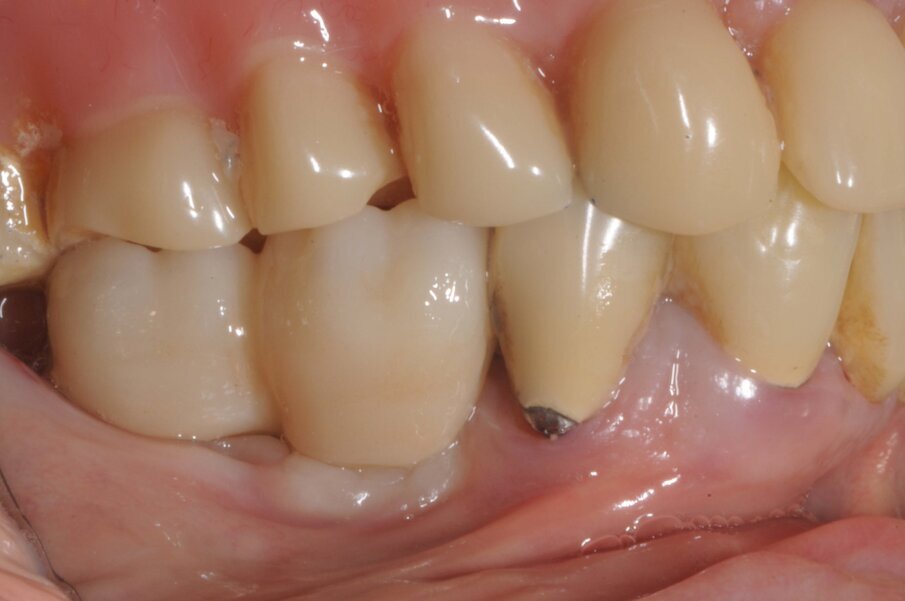

Dopo due messi è stata presa un’impronta con scanner intraorale e due settimane dopo sono state consegnate le corone in zirconio monolitico avvitate.

A sei mesi dalla consegna delle corone è stata eseguita un Rx endoorale di controllo da cui si evidenziava una buona stabilità dell’osso marginale (Fig. 11).